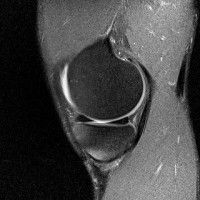

무릎 mri 간단히 봐주실 수 있으시나요 ㅠㅠ

안녕하세요 8년전 십자인대 수술하고 최근 무리한 운동에 무릎 불편감이 생겨서

mri 찍었습니다.

진단결과는 첫 찍은 병원에서 활액막염 이라는 진단을 받았습니다. 혹시 봐주실 수 있으실까요?

올라온 MRI가 단편적이라서 정확한 진단에 어려움이 있지만 십자인대에는 큰 이상이 있지는 않은것 같으며, 무릎관절내 물이 있는 것으로 보아 활액막염의 진단이 맞을 것 같습니다.

하지만 단편적인 영상이기 때문에 촬영병원에서 정확한 판독지 등을 받으시는 것이 좋겠습니다.